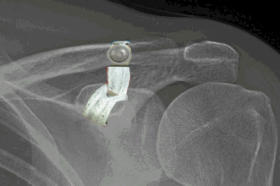

The diagnosis is usually made on the history of the patient falling directly on the point of the shoulder. Pain is felt mostly on the top of the shoulder. Depending on the severity of the injury a bump may be noticeable from the prominent clavicle (collar bone). In minor injuries grade 1 and 2 the x- rays may be normal or nearly normal. If all the ligaments have been injured then the collar bone will be out of alignment usually gone upwards, sometimes backwards and very rarely downwards.  Grade 2 ACJ injury  Note clavicle only slightly elevated  with rupture of ACJ ligaments. The CC ligaments are still intact.  Mouse over for unenhanced x ray Grade 5 ACJ injury Note how high the end of the clavicle is elevated. The ACJ and CC ligaments have completely ruptured and the end of the clavicle has ruptured through the trapezial fascia.  Mouse over for unenhanced x ray   Stress radiographs are sometimes requested although rarely do they alter the final treatment and prognosis.

The diagnosis is usually made on the history of the patient falling directly on the point of the shoulder. Pain is felt mostly on the top of the shoulder. Depending on the severity of the injury a bump may be noticeable from the prominent clavicle (collar bone). In minor injuries grade 1 and 2 the x-rays may be normal or nearly normal. If all the ligaments have been injured then the collar bone will be out of alignment usually gone upwards, sometimes backwards and very rarely downwards.  Grade 2 ACJ injury  Note clavicle only slightly elevated  with rupture of ACJ ligaments. The CC ligaments are still intact. Grade 5 ACJ injury Note how high the end of the clavicle is elevated. The ACJ and CC ligaments have completely ruptured and the end of the clavicle has ruptured through the trapezial fascia. Stress radiographs are sometimes requested although rarely do they alter the final treatment and prognosis.